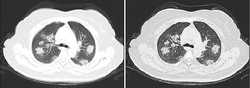

Chest CT scans may be helpful to diagnose COVID‑19 in individuals with a high clinical suspicion of infection but are not recommended for routine screening.[129][141] Bilateral multilobar ground-glass opacities with a peripheral, asymmetric, and posterior distribution are common in early infection.[129][142] Subpleural dominance, crazy paving (lobular septal thickening with variable alveolar filling), and consolidation may appear as the disease progresses.[129][143] Characteristic imaging features on chest radiographs and computed tomography (CT) of people who are symptomatic include asymmetric peripheral ground-glass opacities without pleural effusions.[144]

Many groups have created COVID‑19 datasets that include imagery such as the Italian Radiological Society which has compiled an international online database of imaging findings for confirmed cases.[145] Due to overlap with other infections such as adenovirus, imaging without confirmation by rRT-PCR is of limited specificity in identifying COVID‑19.[144] A large study in China compared chest CT results to PCR and demonstrated that though imaging is less specific for the infection, it is faster and more sensitive.[128]